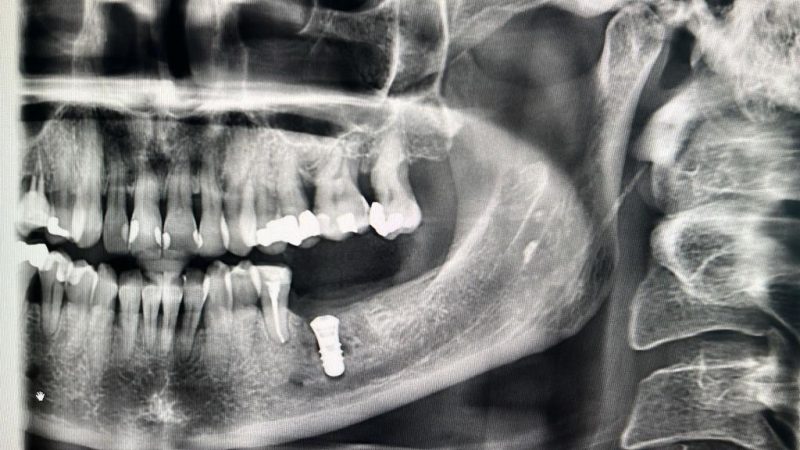

Well THATS not somethin you see every day. And actually the patient was fine. Luckily the drilling was lingual to the actual nerve canal.

Dont try this one at home!

Have a great weekend yall!

• I’d be worried about perforating into the lingual concavity😳